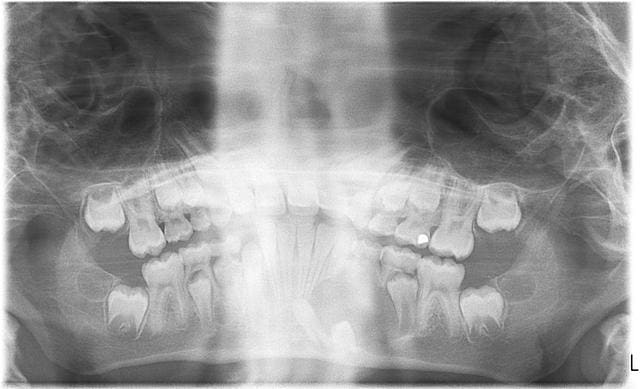

pano comme on a pu

a piori je pense enlever la 74 et compter sur l'élimination spontanée du kyste

pas de chance,c'est au niveau de 74 qu'on ne voit pas gd chose: une petite rx?

cela dit vu l'evolution de 44,mme si léger décalage par comparaison, cela ne doit pas poser de pb

autant pr moi j'ai regardé la 75

la pano n'est vraiment pas terrible,mme le kyste je ne le discerne pas tant(mais où st donc mes lunettes)

par contre tout en bas ,les 2 images,sont les germes de 33 et 34,j'imagine

franchement je ne vois pas gd chose sur ta pano

cependant lapadoué dire que la 74 est saine... euh... pas de carie ,d'accord mais au niveau des racines elles ne me semblent pas d'aspect normal

et puisque kyste il y a on peut s'interroger sur sa vitalité

après avoir trafiqué un peu la pano pr mieux voir,je pensais ext de 73 et 74 sous AG (mais ds un service pedo) à cause du curetage du kyste:il me semble trop important,trop bas et la cicatrisation à cet âge trop rapide pr permettre un drainage naturel suffisant

puis attente 6 mois pr voir l'evolution des germes,l'angulation de 33 laissant préjuger qu'elle va peutêtre demander traction